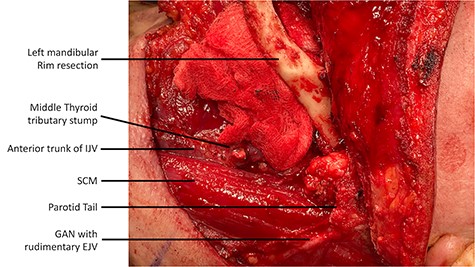

Intraoperatively, during the ND, a rudimentary only external jugular vein (EJV) was identified. Whilst developing the platysma flap, a large venous vessel was identified antero-medially to the SCM and preserved (Fig. 1). This was subsequently found to represent the anterior trunk of the duplicated IJV. Then, when developing the levels II–III–IV of the ND specimen the posterior segment of the IJV was identified and preserved. The course of IJV duplication began at level II under the posterior belly of the DGM. The bifurcation continued to level IV, beneath the omohyoid muscle. Both segments were ~9 cm in length and all the main IJV tributaries (lingual, facial and middle thyroid veins) were draining into the anterior segment (Fig. 2). The space between the two segments was occupied by the common carotid artery, its bulb and its bifurcation. The SAN was found to be running under the two IJV trunks (Fig. 3).

Lateral view of the left neck dissection demonstrating the anterior trunk of the duplicated IJV located antero-medially to the SCM muscle; the dissection of the greater auricular nerve and the presence of a rudimentary EJV is also known.